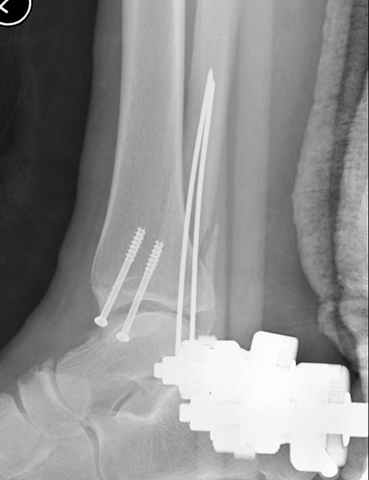

Отправитель: Djoldas Kuldjanov, M.D. 16 Сентябрь 2004, 22:00

Второй случай сделан из одного разреза

ЕЧ LISS plate, mininvasive approach - luxurous !

На прямой проекции послеоперационного Рг макроскопически все выглядит очень анатомично, при микроскопическом ( :-)) ) рассмотрении можно все-таки заметить вальгизацию тарана, суставная щель в латеральном отделе сустава несколько уже , чем в медиальном при отсутствии латерального смещения тарана. У меня был аналогичный случай (без LISS , без мини доступа) с вальгусным наклоном тарана при восстановленном ankle mortise при последовательном наблюдении с интервалами в 6-8 недель в послеоперационном периоде отмечалось прогрессирующее сужение суставной щели в латеральном отделе сустава, закончившееся посттравматическим ОА, к счастью боли умеренные, купируемые аналгетиками или своими эндорфинами:-))(активная пациентка, у которой нет времени на болезни....) Какова жизненная ситуация в приведенном вами случае? И последнее, что я хотел бы прояснить для себя - фиксация внутренней лодыжки: я обычно комбинирую фиксацию компрессирующим винтом со спицей - по идее ротационная стабильность должна быть лучше, чем один винт, каковы ваши наблюдения в этом плане?